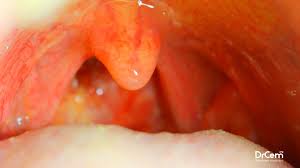

Tonsil muayenesi Kızarıklık, bademcik büyümesi, bazen beyaz püskürme Tonsil itilir, peritonsiller bölgede şişlik ve yanak/yan duvarda çıkıntı

Asimetri Genellikle simetrik Tonsiller arasında asimetri (etkilenen tarafta daha belirgin)

Ağız içi asimetri, uvula deviasyonu

• Ağız içinde bir taraf şişmiş/itilmiş görünür

• Uvula (dil ucunun arkası) karşı tarafa deviye olabilir